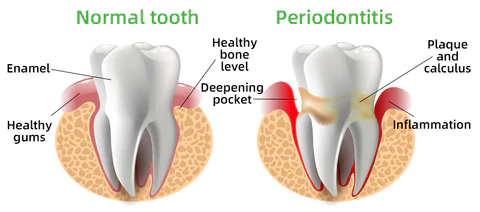

Every day, food residues in our mouths create a breeding ground for various bacteria and microorganisms within the oral cavity. This can result in a range of oral health issues, including bad breath, mouth ulcers, yellow teeth, cavities, calculus buildup, gum inflammation, bleeding gums, tooth sensitivity, weakened or missing teeth, swollen gums, toothaches, loose teeth, tooth loss, and even the risk of oral cancer.

As these conditions worsen, you may experience persistent bad breath, gum inflammation, and other problems. Bacteria continue to harm your gums, leading to issues like bleeding, pain, and redness. Without timely intervention, these oral problems can escalate, potentially causing periodontitis, dental plaque, dental calculus, loose teeth, tooth pain, and eventually tooth loss.